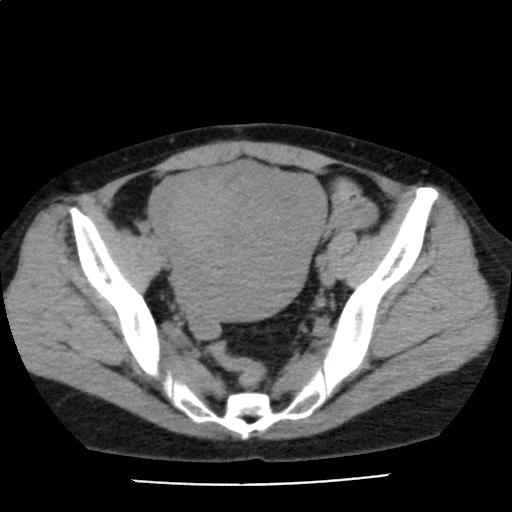

子宮腫大を認め、筋腫が疑われるが、臨床経過との対比が望まれる

腹部に有意なリンパ節腫大は認めない。少量の腹水を認める。

子宮腫大